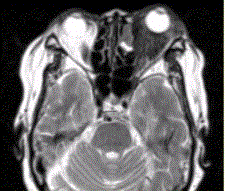

患者女,64岁,左眼突出5年余。查体左眼球前突6mm,眼球运动自如,眼底无异常,下睑扪及边界不清、质软的肿块,视力正常,MR表现如下图。临床拟...

问题 患者女,64岁,左眼突出5年余。查体左眼球前突6mm,眼球运动自如,眼底无异常,下睑扪及边界不清、质软的肿块,视力正常,MR表现如下图。 临床拟诊为

选项 A.眶内炎性假瘤 B.眼型Grave病 C.黑色素瘤 D.转移瘤 E.眼眶海绵状血管瘤 F.弥漫型淋巴管瘤

答案 A

解析 A